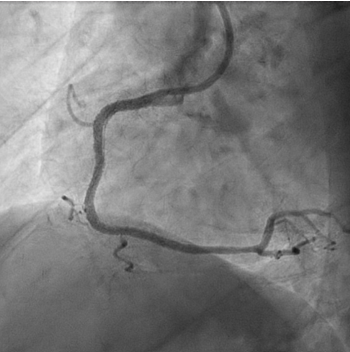

Coronary angioplasty was performed by first advancing a Sion guidewire (Asahi), followed by a Launcher Amplatz right 6F guide catheter (Medtronic) with a 2.5 x 15-mm semicompliant balloon. Next, a 3 x 48-mm everolimus-eluting stent was advanced with a GuideLiner 6F extension catheter (Teleflex). After inflation, the stent failed to expand as a result of perforation of the drug-eluting balloon (Figure 2); only partial opening of the ends of the stent was observed, with consequent entrapment of the stent and balloon. Traction proved unsuccessful for retrieval of the device and the balloon hypotube shaft was torn; consequently, the device was lost in the right coronary artery.

In view of this complication and the clinical instability of the patient, extraction of the device with a coronary snare was attempted but was unsuccessful (Figure 3). The access route was then changed to the femoral artery using an Amplatz left 6F catheter, and a Sion guidewire was advanced to the distal segment of the right coronary artery with the support of a 135-cm FineCross microcatheter (Terumo). This was followed by dilatation using a Sapphire II PRO balloon (OrbusNeich) (Figure 4) with catheter extension and anchoring of the balloon until 2 new everolimus-eluting stents (2.5 x 40 mm and 3.0 x 15 mm) could be advanced (Figure 5). Upon post-dilation of the noncompliant balloon, the previous stent and ballon were successfully crushed, obtaining a good final angiographic result (Figure 6). The procedure was completed with intracoronary optical coherence tomography, which confirmed adequate stent expansion and apposition, as well as the crushing of both the stent and the previous balloon (Figures 7-11).